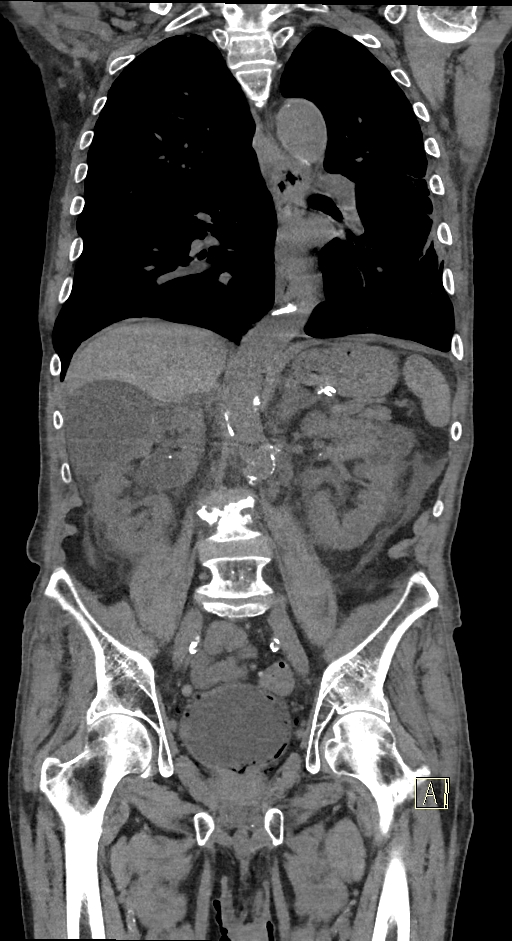

Figurile 1 şi 2: axial examinare CT abdomen şi pelvis fără substanță de contrast

Figurile 4 şi 5: coronal examinare CT abdomen şi pelvis fără substanță de contrast

Discuţie caz nr 131: pacient de 85 de ani cunoscut diabetic este adus la camera de gardă pentru dureri abdominale difuze, efectueaza CT fără substanță de contrast deoarece eGFR este 21 mL/min/1.73 m². Se evidențiază pericardita în cantitate medie, mai multe chiste renale – unul spontan hiperdens, multiple plăci aterotrombotice calcificate la nivelul aortei și ramurilor precum și multiple bule aerice în peretele vezicii urinare și conținut hidro-aeric al vezicii urinare. Ultimele două elemente sugerează diagnosticul de cistita emfizematoasă.